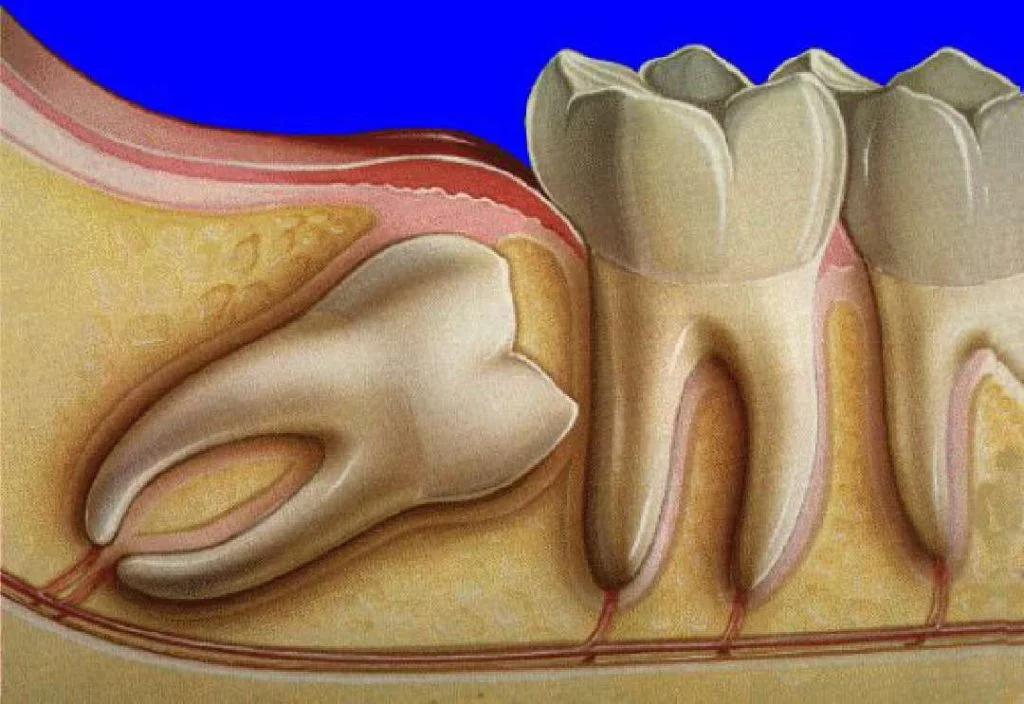

Найчастіше проблеми виникають, коли зуб росте під кутом, тисне на сусідні зуби або частково прорізається. У таких випадках може з’являтися біль, запалення ясен або навіть інфекція.

Чому виникають проблеми із зубом мудрості

Причини можуть бути різні, і часто вони пов’язані не тільки з анатомією.

Основні фактори:

- нестача місця у щелепі

- неправильний ріст зуба

- часткове прорізування

Видалення зуба мудрості / фото lukashuk

Як відбувається видалення зуба мудрості

Складність залежить від того, як розташований зуб. Якщо він ретинований або росте під кутом, процедура займає більше часу.

Зуб мудрості / фото ukrdentclub